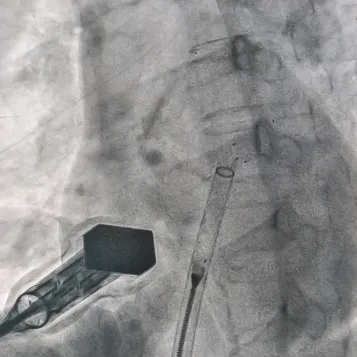

左盘展开

DSA下推出前4个显影点,展开左盘

左盘展开后,轻拉成型线使盘面成型,再将输送系统整体后撤贴靠房间隔

右盘展开

固定钢缆后撤鞘管,展开右盘

封堵器锁定成型后,牵拉试验可见5个显影点整体随钢缆移动,右盘显影点未发生明显位移